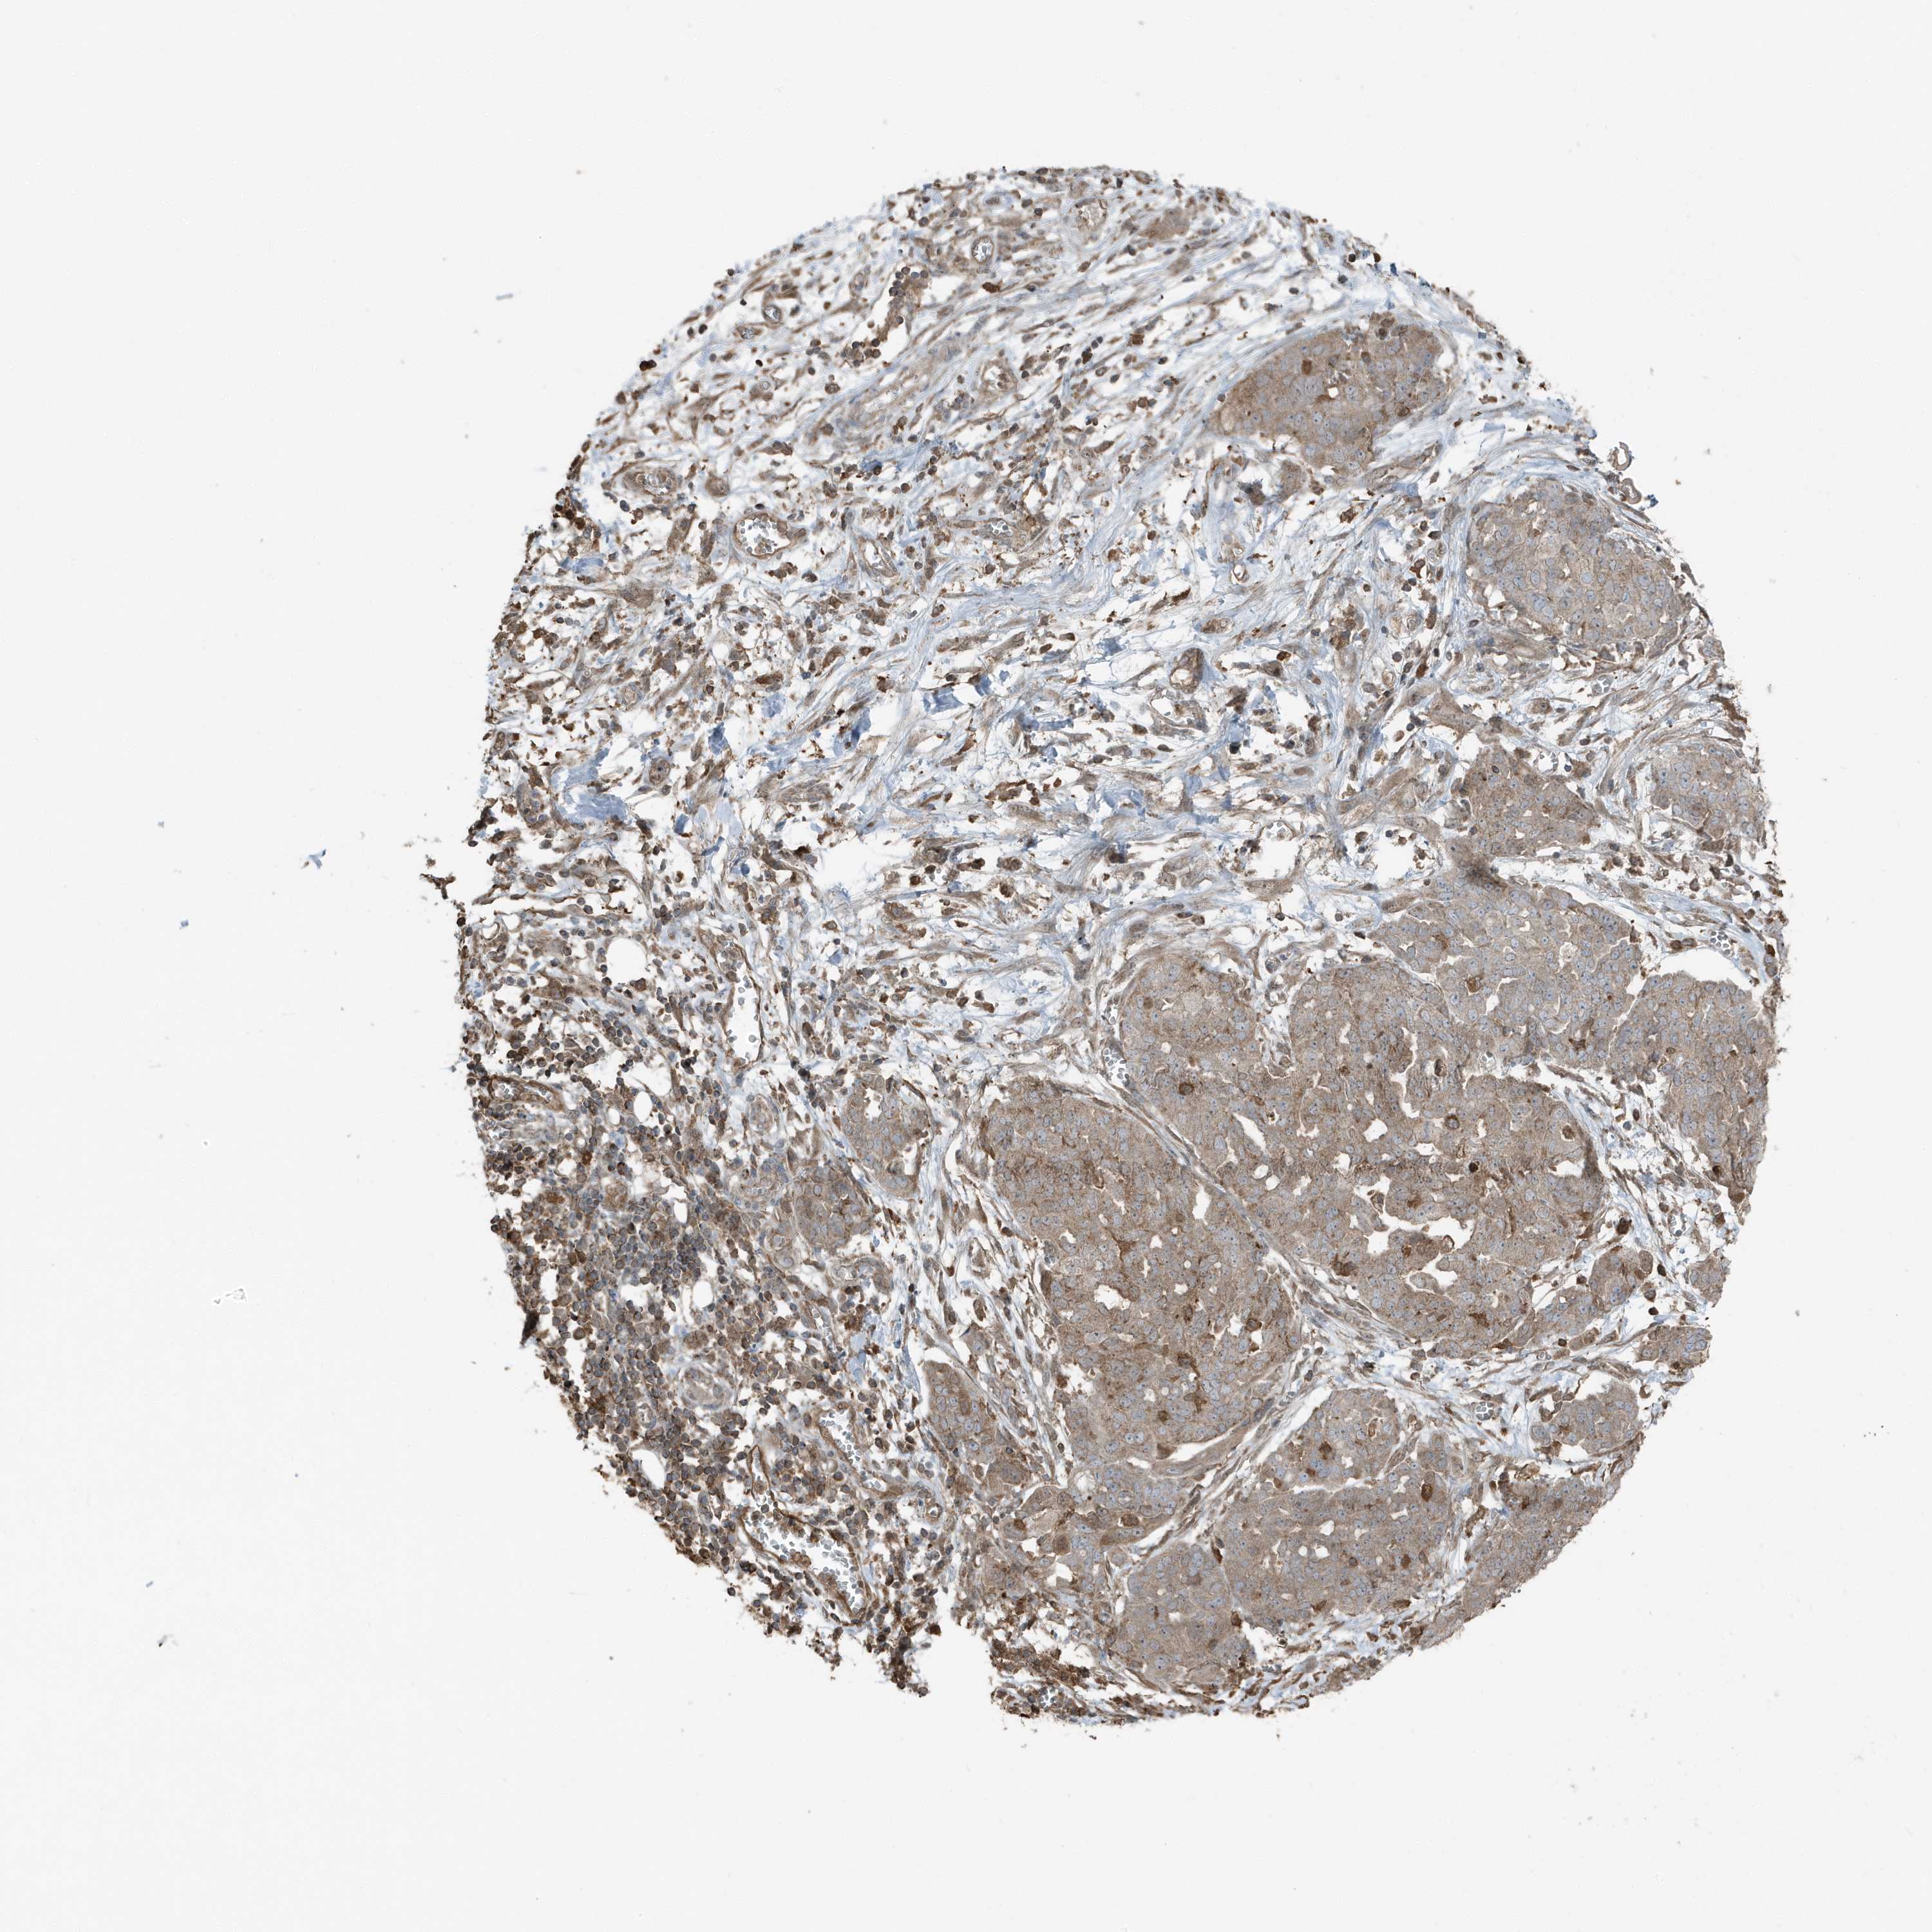

OVARIAN CANCER - Protein expressioni

A mouse-over function shows sample information and annotation data. Click on an image to view it in a full screen mode. Samples can be filtered based on level of antibody staining by selecting one or several of the following categories: high, medium, low and not detected. The assay and annotation is described here.

Note that samples used for immunohistochemistry by the Human Protein Atlas do not correspond to samples in the TCGA dataset.

Antibody stainingi

Antibody staining in the annotated cell types in the current human tissue is reported as not detected, low, medium, or high, based on conventional immunohistochemistry profiling in selected tissues. This score is based on the combination of the staining intensity and fraction of stained cells.

Each image is clickable and will lead to virtual microscopy that enables deeper exploration of all samples and also displays staining intensity scores, fraction scores and subcellular localization as well as patient and tissue information for each sample.

Antibody HPA035258

Staining

High

Medium

Low

Not detected

Intensity

Strong

Moderate

Weak

Negative

Quantity

>75%

75%-25%

<25%

None

Location

Nuclear

Cytoplasmic/membranous

Cytoplasmic/membranous,nuclear

Cystadenocarcinoma, serous, NOS

Carcinoma, endometroid

Cystadenocarcinoma, mucinous, NOS

Carcinoma, NOS